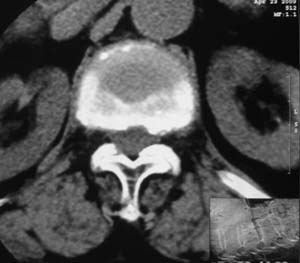

患者,女,72岁,胸背部疼痛3月余,无明显外伤史。曾应用局部封闭、非甾体类止痛药治疗效果不明显,近来疼痛缓解频感背困,平卧缓解,近日行ct检查发现胸12椎体病变,烦请同道发表意见,诊断什么?有何治疗经验!谢谢!!!

标绘图示:第十二胸椎级第一腰椎椎体楔形改变。ct扫描示:第十二胸椎椎体骨质结构紊乱,并可见一囊状低密度影,边缘可见硬化,椎体皮质完整。

考虑:第十二胸椎陈旧性骨折、许莫氏结节。